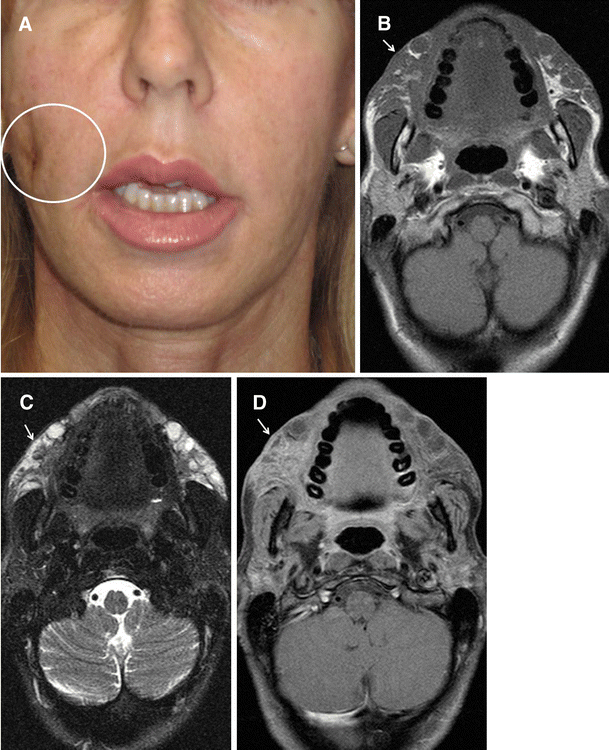

coronal t1 resonance imaging (mri) of the face mri was carried

coronal t1 resonance imaging (mri) of the face mri was carried Dermal Piercing Face Mri Safety Mri scanning of a patient with dermal piercings is not ideal as some dermal piercings can have magnetic. Body piercing jewelry and mri safety. Particularly fresh piercings that can’t safely be removed, or surface piercings like microdermals and surface bars? Body piercing jewelry and mri safety. Well, let’s take a look. Patients with dermal piercings undergoing mr exams page 66. Dermal Piercing Face Mri Safety.